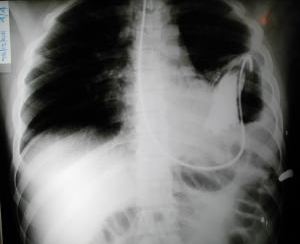

Radiología del tórax:

Sonda nasogastrica con contraste

Evidencia el fundus gastrico en la base del hemi tórax izquierdo, (contraste digestivo y la sonda llena de contenido radiopaco), unión cardioesofagica in situ, anillo o brecha diafragmática, borramiento del seno costo diafragmático  y borramiento de la linea diafragmática Izquierda, se confirma la presencia de hernia diafragmática Izquierda.